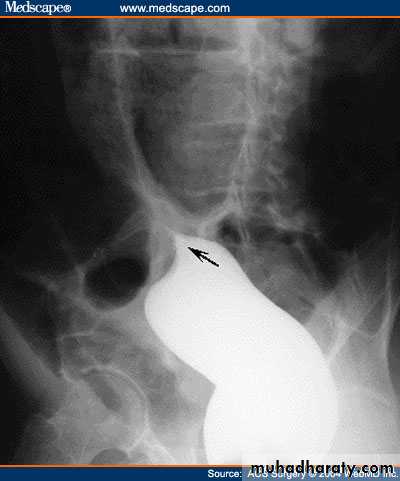

Ba enema will show smooth tapered narrowing with marked dilatation of proximal bowel